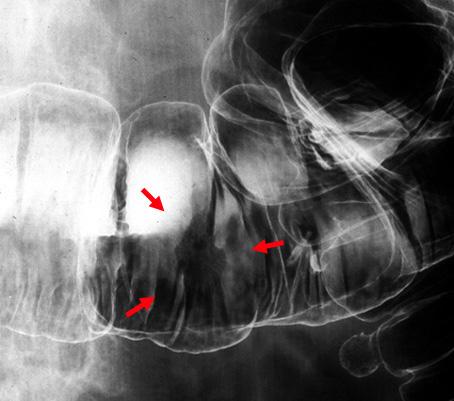

疾患(病理主体)の分類悪性上皮性腫瘍/腺癌

部位(臓器別)大腸/横行

検査方法X-P

腫瘍の肉眼分類0型(表在型)/IIc型(IIc)

病変の最大径(ミリ)15〜19

腫瘍の深達度m